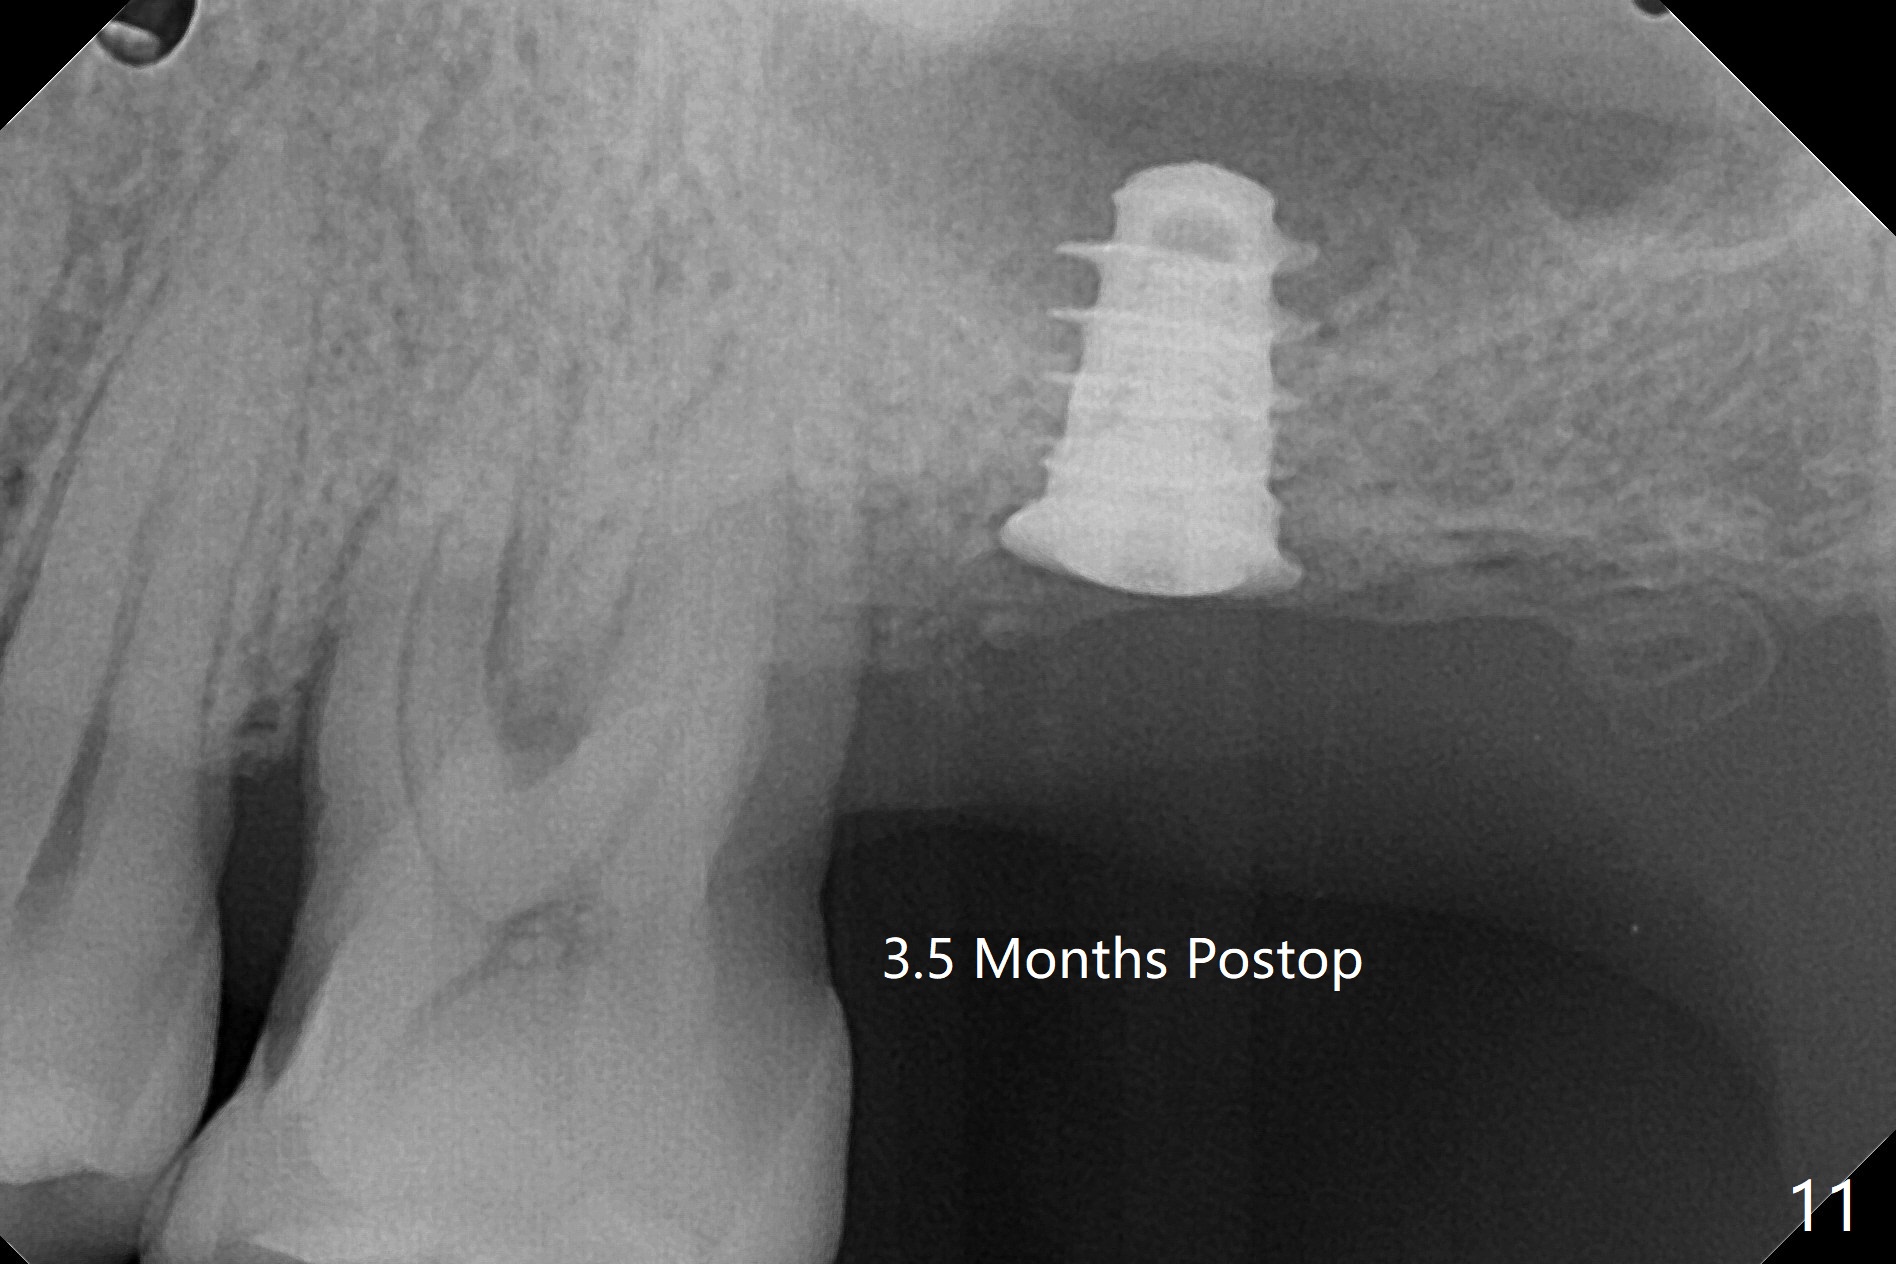

implant is stable upon uncover 3.5 months postop (Fig.11).

一个月后安置修复基台,开始progressive loading,临时牙冠没有咬合。